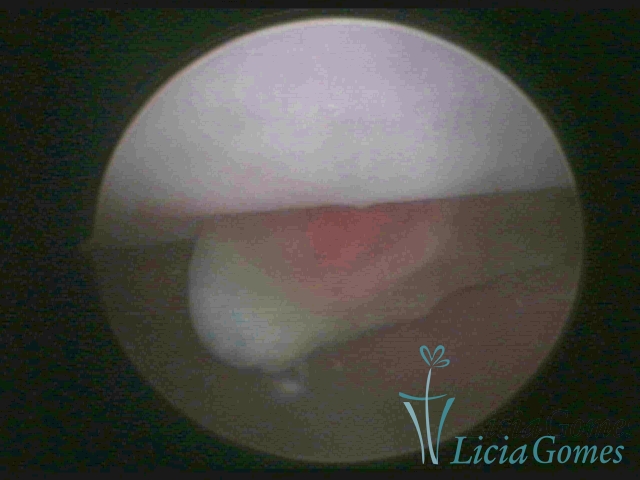

ENDOCERVICAL POLYPS

Benign tumors resulting from the reactive focal proliferation to inflammatory processes or hyperestrogenism situations, which may be sessile (with a large implantation) or stalked.